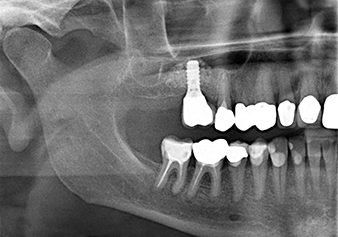

49-летняя пациентка, некурящая и не имеющая ничего примечательного в общей истории болезни, была направлена в нашу хирургическую стоматологическую клинику для хирургического удаления зуба 16 и последующей имплантации. После удаления зуба пациентка перенесла синусит в легкой форме, в результате чего мы сначала выждали шесть месяцев перед проведением операции. Остаточная высота кости при запланированном положении имплантата составляла 3-4 мм (рис. 1 и 2).